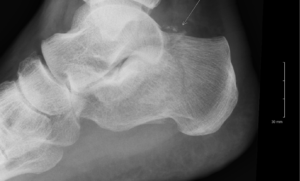

При выявленном заболевании плантарного фасциита (так называется пяточная шпора) специалист даёт подробное описание снимка, где отмечает наличие остеофита с указанием его длины и локализации. Обычно остеофиты на снимке видны в проекции верхнего края задней бугристости таранной кости.

Другой распространённой проблемой считается такое заболевание стопы, как пяточная шпора. Возникает оно по причине ношения неправильной обуви, развития артрита или артроза, но чаще всего из-за сформировавшегося плоскостопия.

Если данную болезнь не лечить, она может вызывать такие осложнения, как подпяточный бурсит (воспаление слизистых сумок) и фасциит (воспаление мышечной ткани стопы).

На снимке довольно четко могут визуализироваться новообразования на кости пятки. В этом случае оцениваются: их размер и локализация, – после чего делается вывод о возможной природе отклонения.